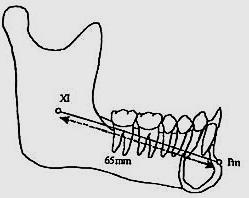

Alteraciones faciales

Todos los dientes intervienen en la conformación de una oclusión ideal, así como del volumen facial en el tercio medio e inferior de la cara. Es el caso, que la presencia del canino superior permanente en la arcada en el tiempo cronológico adecuado, es muy importante para el desarrollo óseo del tercio medio facial, ya que estimula el crecimiento del maxilar tanto en el área lateral del ala de la nariz bilateralmente, como en la pared anterior del macizo óseo, lo cual, evita el hundimiento facial de la parte inferior del pómulo y la rectificación facial de los músculos en esta área15 (Figura 34).

Respecto al desarrollo del tercio inferior de la cara, la presencia de los caninos inferiores en el arco dental es el complemento correcto e ideal para el desarrollo mandibular y facial del

tercio inferior, al coordinarse con los caninos superiores en todos los movimientos fisiológicos, como la masticación18 (Figura 35).

El desarrollo y crecimiento mandibular a nivel de la rama, cuerpo y parte anterior en la zona del mentón, depende en parte de la presencia del canino, para efectuar correctamente los movimientos esenciales de lateralidad, protrusión, cierre adecuado de la mordida, además de armonizar el desarrollo correcto de la curva en la arcada dental en el plano transversal o de Wilson, así como de la curva sagital anteroposterior o de Spee19,20 (Figura 36).

La dinámica muscular